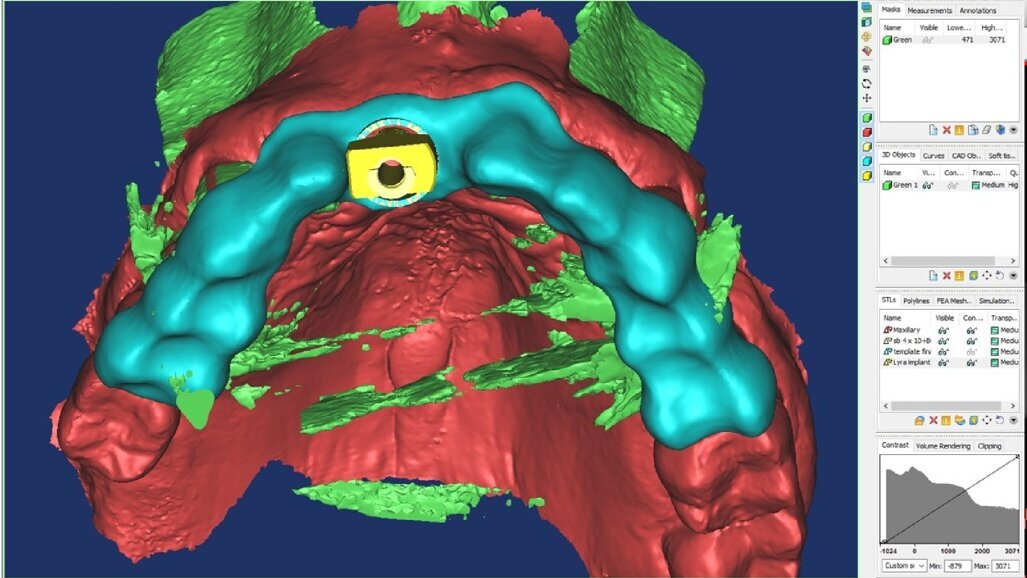

I dati Digital Imaging and Communication in Medicine (DICOM) derivanti dalla CBCT, insieme con il file standard tesselletion language (.STL) ottenuto tramite la scansione intraorale, venivano quindi caricati in cloud in un software di Intelligenza Artificiale (Virtual Patient Creator, RELU). Tali dati venivano elaborati e il software di Intelligenza Artificiale restituiva, in meno di 10 minuti, la ricostruzione 3D della maxilla del paziente, ottenuta tramite segmentazione ossea automatica, accoppiata e allineata alla scansione intraorale (Fig. 4). Il software, inoltre, restituiva la segmentazione di ciascun singolo elemento dentario, sotto forma di files .STL separati, nei quali la corona veniva direttamente dalla scansione intraorale, mentre la radice dalla CBCT (Fig. 5). La “fusione” automatica del dato della CBCT con quello della scansione intraorale, e il perfetto allineamento tra le strutture anatomiche, rappresentava il risultato dell’applicazione dell’Intelligenza Artificiale. La stessa area rigenerata veniva opportunamente segmentata (Fig. 6). A questo punto, l’operatore era in grado di visualizzare tutte le strutture, selezionare quelle interessanti ed esportarle come files .STL. Tali files venivano quindi caricati all’interno di una applicazione dedicata per l’uso per la realtà aumentata (Holodentist, Fifthingenium), insieme con la libreria implantare del sistema scelto (Naturactis, Lyra ETK) per la risoluzione dello specifico caso clinico (Fig. 7). L’operatore vestiva quindi gli occhialini per la Realtà Aumentata (MagicLeap2, Magic Leap) e, anche attraverso l’aiuto di uno specifico joypad, era in grado di pianificare l’impianto in 3D nell’esatta posizione, profondità ed inclinazione, impiegando gli ologrammi (Clicca QUI). Terminata la pianificazione e salvata la posizione dell’impianto, essa veniva esportata e impiegata per disegnare, all’interno di software open-source, un template per una chirurgia guidata statica (Figg. 8, 9). Dal momento che Intelligenza Artificiale e Realtà Aumentata non possiedono ancora le certificazioni per l’impiego clinico, tutti i files erano quindi re-importati all’interno di software radiologico certificato (MIMICS, Materialise) per il controllo della posizione implantare nelle cross-sections radiologiche (Figg. 10, 11).

Fig. 10_Controllo della qualità della pianificazione olografica in software certificato (MIMICS, Materialise).